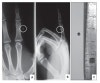

엑스레이 사진을 여러 각도로 찍어 보는 것이 도움이 됩니다.

X-ray : 피부 밑 이물(Subcutaneous foreign body)